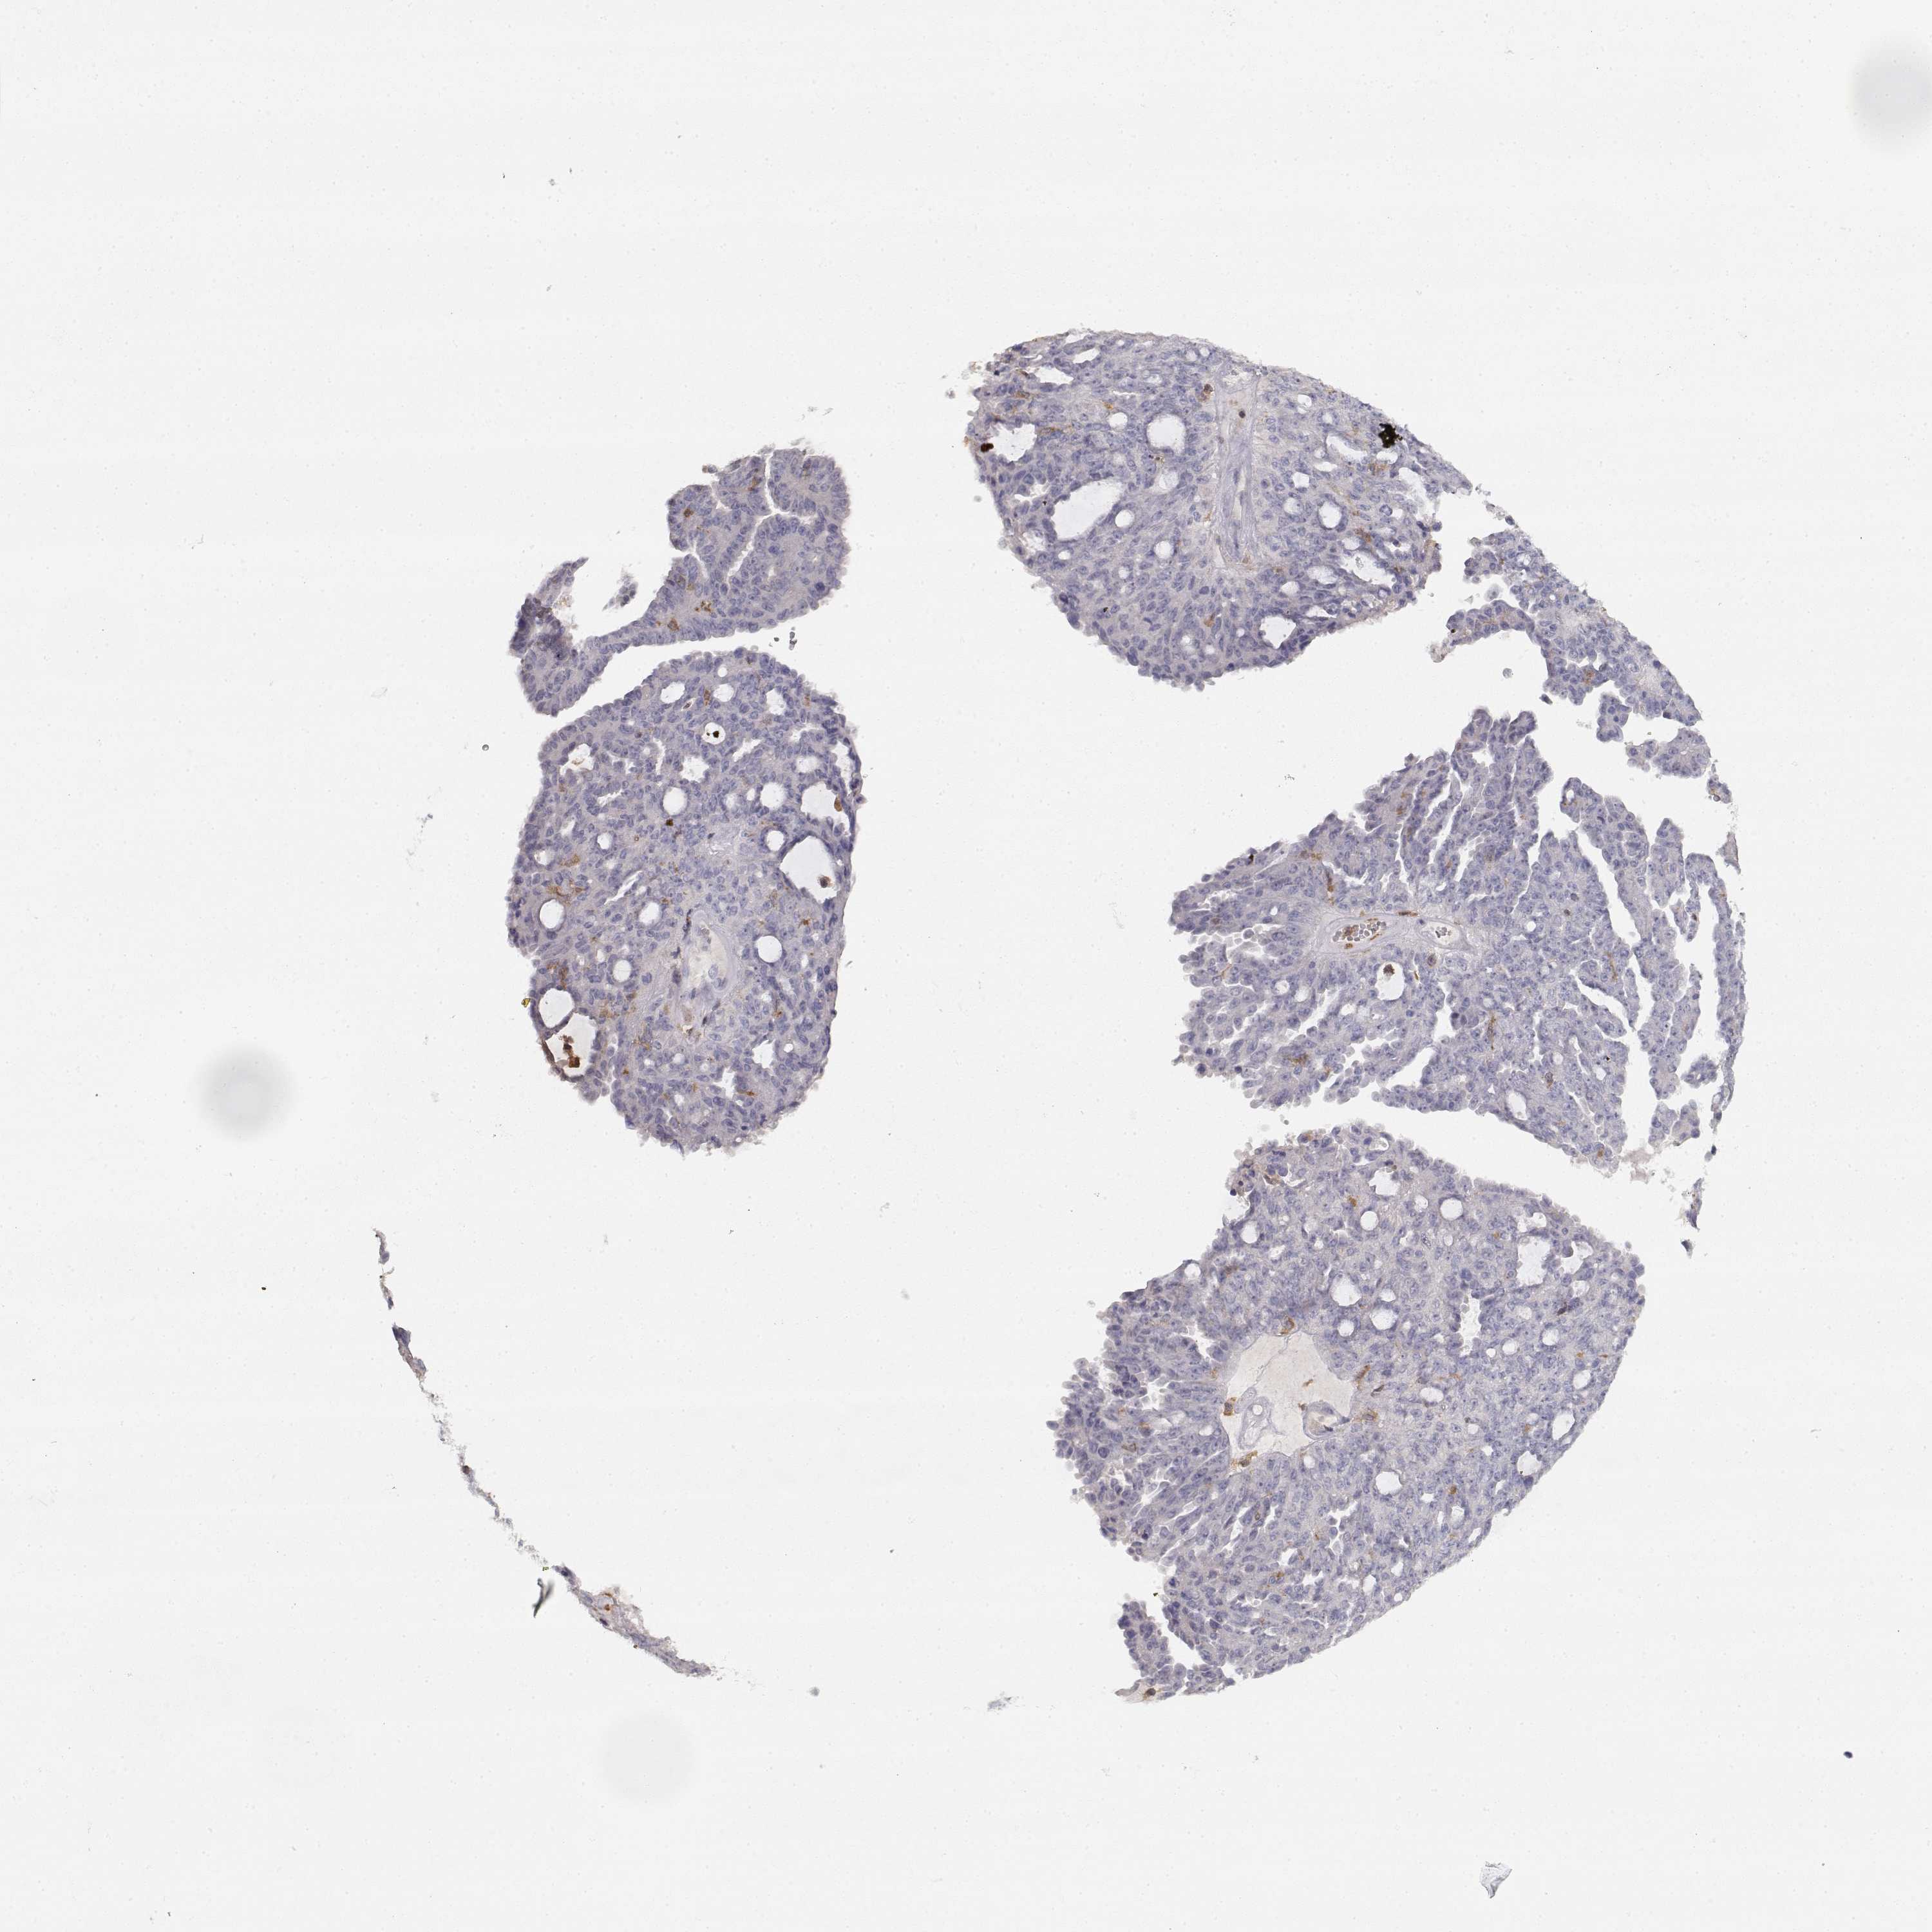

OVARIAN CANCER - Protein expressioni

A mouse-over function shows sample information and annotation data. Click on an image to view it in a full screen mode. Samples can be filtered based on level of antibody staining by selecting one or several of the following categories: high, medium, low and not detected. The assay and annotation is described here.

Note that samples used for immunohistochemistry by the Human Protein Atlas do not correspond to samples in the TCGA dataset.

Antibody stainingi

Antibody staining in the annotated cell types in the current human tissue is reported as not detected, low, medium, or high, based on conventional immunohistochemistry profiling in selected tissues. This score is based on the combination of the staining intensity and fraction of stained cells.

Each image is clickable and will lead to virtual microscopy that enables deeper exploration of all samples and also displays staining intensity scores, fraction scores and subcellular localization as well as patient and tissue information for each sample.

Antibody HPA001864

Staining

High

Medium

Low

Not detected

Intensity

Strong

Moderate

Weak

Negative

Quantity

>75%

75%-25%

<25%

None

Location

Nuclear

Cytoplasmic/membranous

Cytoplasmic/membranous,nuclear

Cystadenocarcinoma, serous, NOS

Cystadenocarcinoma, mucinous, NOS

Carcinoma, endometroid